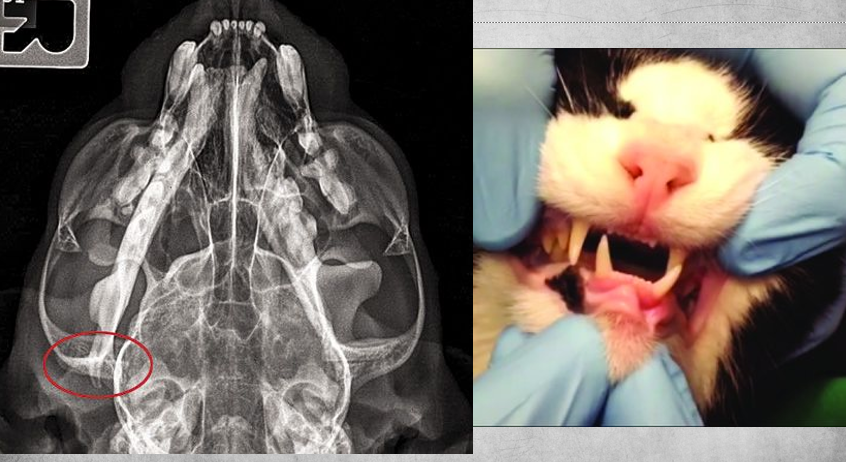

23

TMJ luxation in a cat